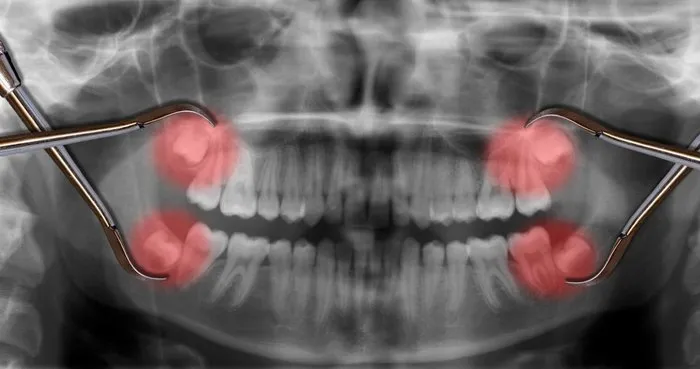

Yirmilik diş birçok insana sıkıntı verir ve çektirilmek zorunda kalınır.

Diş çekiminden sonra ne zaman yemek yenir. Diş çekiminden sonra ne zaman yemek yenir diye merak ediyorsanız eğer minimum 2 ya da 3 saat beklemeniz faydalı olacaktır. Diş çekiminden ne zaman sonra yemek yenir sorusu çekim işleminden sonra en çok araştırılan konular arasında. 6 11 gömülü 20 lik diş çekimi sonrası ağrı ne kadar sürer. Ağız ve diş sağlığı açısından öncelikle dişi tedavi etmeyi amaçlasalar da çeşitli sağlık sorunları yüzünden diş kayıpları da yaşanıyor.